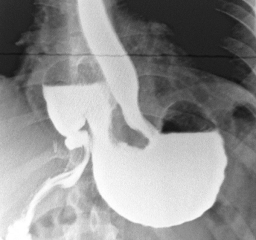

Рентгенография верхних отделов ЖКТ представляет

собой рентгенологическое исследование глотки, пищевода, желудка и начальных

отделов тонкого кишечника (двенадцатиперстной кишки). Для получения изображений

используется особая разновидность исследования под названием флюороскопия и

вводимый перорально (через рот) контрастный материал в виде бария.

Рентгенография глотки Рентгенография пищевода

Рентгенография желудка Контрастная

рентгенография тонкого … кишечника

Рентгеноскопия верхних отделов пищеварительного

тракта (глотки, пищевода, желудка и двенадцатиперстной кишки) до настоящего

времени остается одним из основных методов диагностики злокачественных

новообразований этих органов. В современной рентгенодиагностике все четыре

перечисленных органа исследуются одновременно. Особое значение имеет

возможность обнаружения опухолей, обладающих интрамуральным (внутри стенки) или

экзоорганным (кнаружи от стенки органа) ростом, а также новообразований

соседних органов, которые не видны при эндоскопических исследованиях.